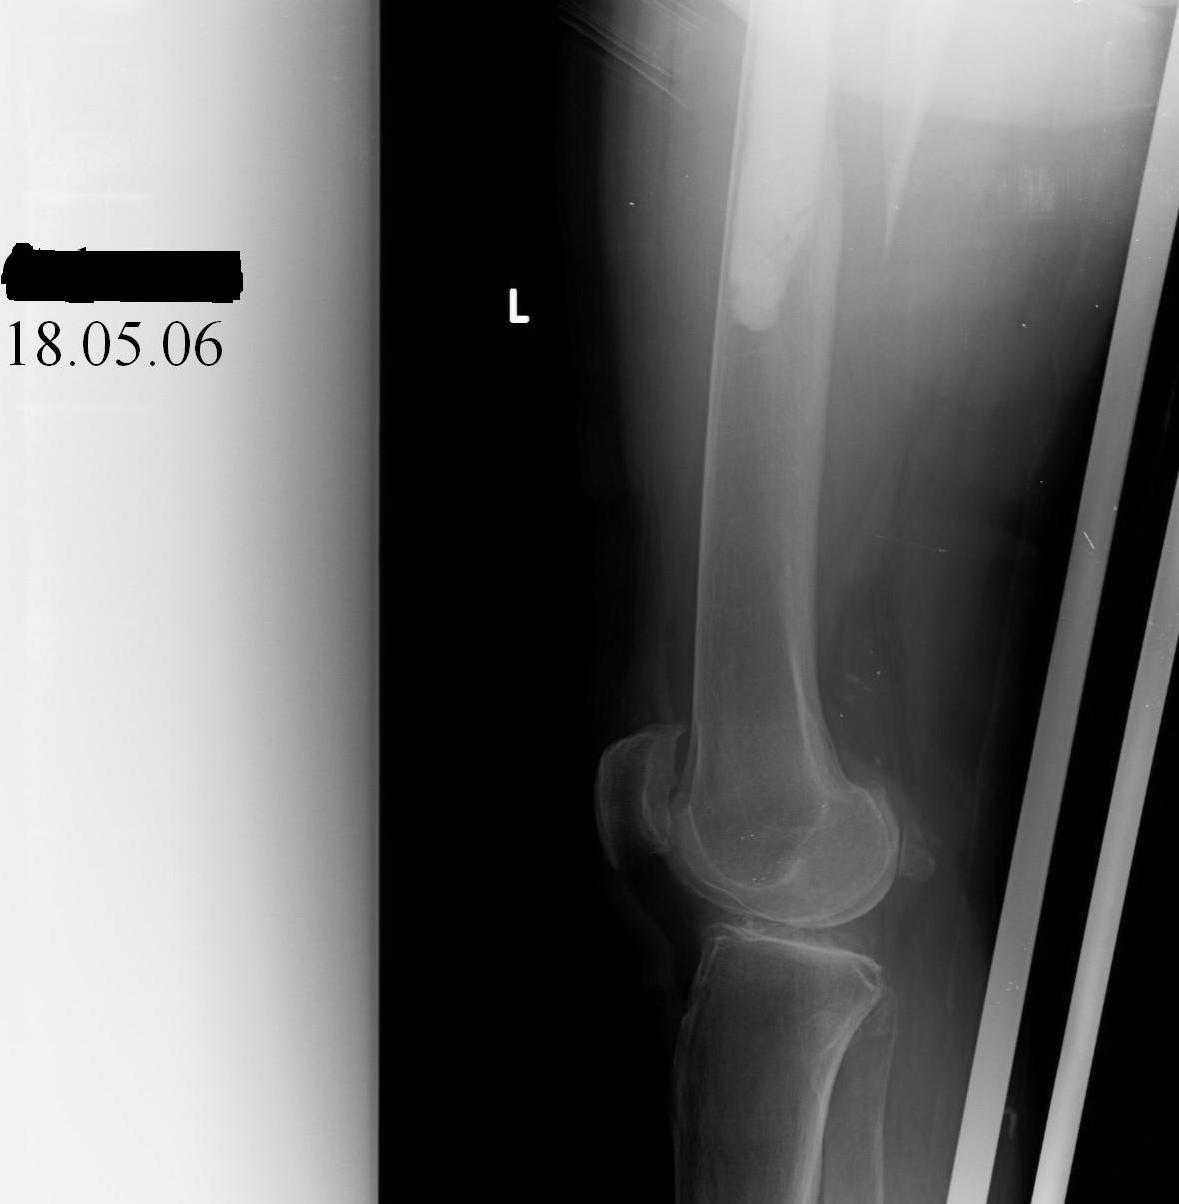

Hello! This is just illustration in one of the choice of treatment